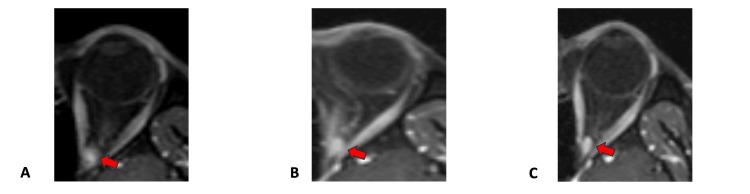

立体定向放射外科治疗眶尖血管肿瘤后的视力改善

Visual Improvement Following Stereotactic Radiosurgery for Orbital Apex Vascular Tumor.

Orbital apex lesions represent a clinical challenge since they are difficult to remove surgically and may induce significant functional defects. The orbital apex is an area of convergence of neurovascular elements passing through the various local osseous foramina and the congestion of several critical anatomical structures in a confined space increases the risk of intraoperative complications. Radiotherapy is an alternative treatment option in such cases but may also induce radiation toxicity. We present a case of a vascular orbital apex lesion, which caused vision loss and was treated with stereotactic radiosurgery, resulting in significant visual restoration.

摘要